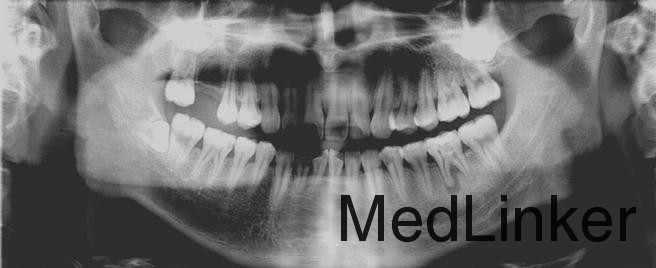

曲面断层片检查